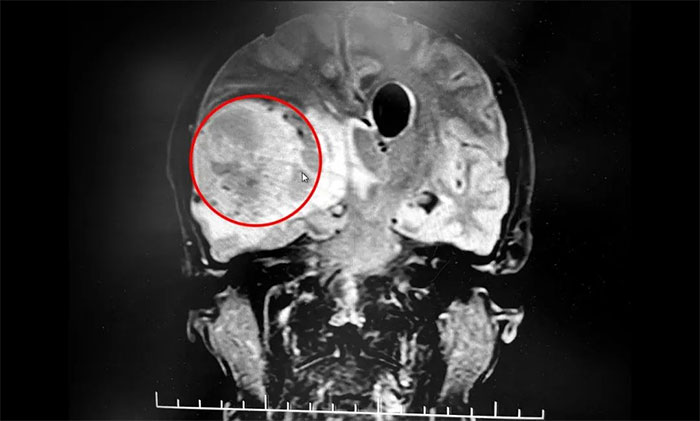

▲ MRI檢查,提示鴨蛋大小腦腫瘤

急行頭顱MRI檢查,提示:右側(cè)額顳葉見團塊狀不均勻異常信號影,周圍見明顯水腫信號,增強后呈明顯花邊樣強化,壁薄厚不均,內(nèi)壁欠光滑,中央?yún)^(qū)未見強化,病灶大小約5.6*4.4*5.1cm,側(cè)腦室受壓及腦干、第三腦室變窄,中線結(jié)構(gòu)向左移位,左側(cè)側(cè)腦室擴大?紤]為高級別腦膠質(zhì)瘤伴腦疝形成。

患者顱內(nèi)有一枚鴨蛋大小的腦腫瘤,病情進展迅速,已因顱內(nèi)壓增高出現(xiàn)腦疝。若腦干等重要腦組織持續(xù)受壓,可在短時間出現(xiàn)功能衰竭,危及患者生命。